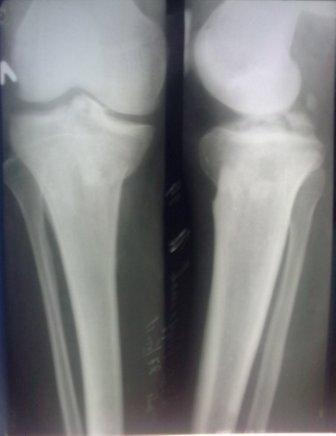

Сегодня обратился больной 35л. Травму получил 3 мес.назад, упал в яму, лечился в отдаленном районе гипсовой повязкой, 1 месяц назад гипс сняли , и больной начал ходить с нагрузкой, постепенно появилась деформация коленного сустава, неустойчивость  и боли. Локально: деформация коленного сустава, голень смещена кзади- типа подвывиха,    разгибание 170гр. Сгибание  150гр.симптомов повреждение боковых коллатеральных

и крестообразных связок определить не удается из-за боли и контрактуры.

Первичных снимков пока нет, обещали принести, имеется снимки через 2 месяца после травмы без гипса, недельной давности снимки в прямой проекции и К Т. Похоже, что импрессия  переднемедиальной  части внутреннего мыщелка б/берцовой кости, отрыв межмыщелкового возвышения.

Мы первым этапом –тепловые физпроцедуры, усиленная разработка движений в течении 2-3 недель до возможного восстановления; после повторный осмотр для решения дальнейшего лечения; возможно- поднятие мыщелка,  дефект аутографтом , фиксация мыщелковой пластиной, а что делать с межмыщелковым  возвышением и подвывихом- пока не знаю.